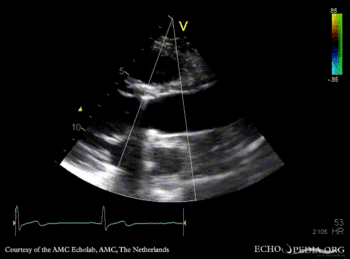

Bentall and aortic valve prosthesis

Courtesy of: AMC Echolab, AMC, The Netherlands

PLAX: aortic valve prosthesis and Bentall in situ PLAX with Color Doppler